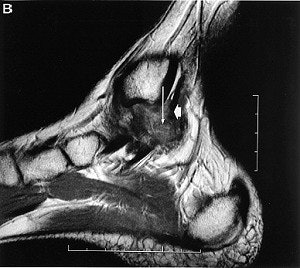

Coronal (A) and sagittal (B) MR images of PTTL injury

(arrow) with marked scar formation and hypertrophic response. The medial collateral ligament is lifted off the bone strictures of the medial ankle gutter by the volume scar formation. Encasement of the tibialis posterior tendon is noted (arrowhead). These findings are confirmed on ultrasound (C), which also detects the presence of calcific densities in the ankle gutter, either as a result of avulsion or dystrophic calcification.